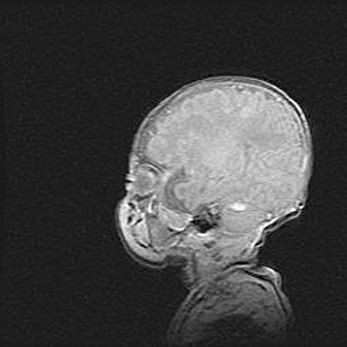

Лейкомаляция с кистозно-глиозной дегенерацией головного мозга.

Возраст: 2 месяца 25 дней

Вес: 6400 г

Окружность головы: 40 см

Срок гестации: 41 неделя

Лейкомаляцию относят к ишемически-гипоксическим повреждениям головного мозга, диагностируемым у новорожденных. При лейкомаляции в головном мозге обнаруживают очаги некроза, возникшие после тяжелой гипоксии и нарушения кровотока. В процессе морфогенеза очаги проходят три стадии: 1) развития некроза, 2) резорбции и 3) формирования глиозного рубца или кисты. Перивентрикулярная лейкомаляция (ПЛ) встречается примерно в 12% случаев среди новорожденных, обычно – у недоношенных детей, причем, частота ее зависит от массы, с которой младенец появился на свет. Наибольшее число малышей страдает лейкомаляцией, если масса при рождении 1500-2500 г.